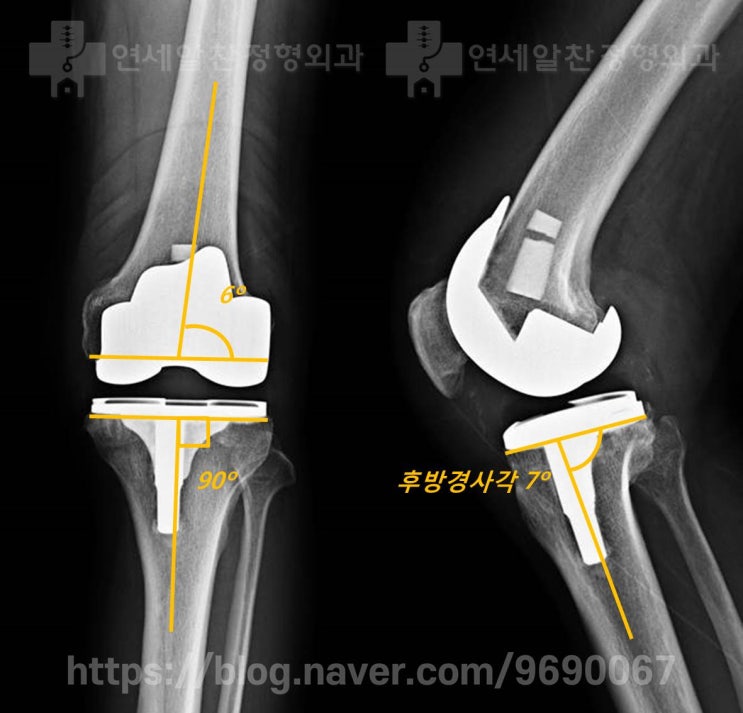

무릎 퇴행성 관절염에서 인공관절 전치환술 및 결과에 대한 고찰

71세 여자 환자로 10년 이상의 무릎 통증을 주소로 내원하였다. 환자는 약물 및 연골주사, 통증주사 를 반...